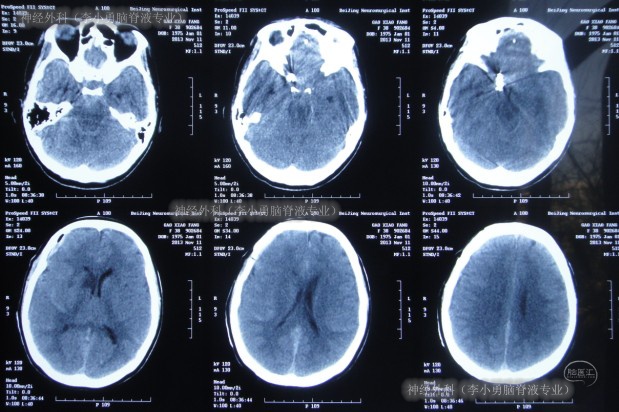

继续治疗14天内,患者逐渐出现表情呆滞,反应迟钝,昏睡,在2013年12月2日即动脉瘤夹闭术后28天,复查头颅CT示脑室扩张加重及脑室周围水肿明显(图-6)。

图-6:术后28天头颅CT